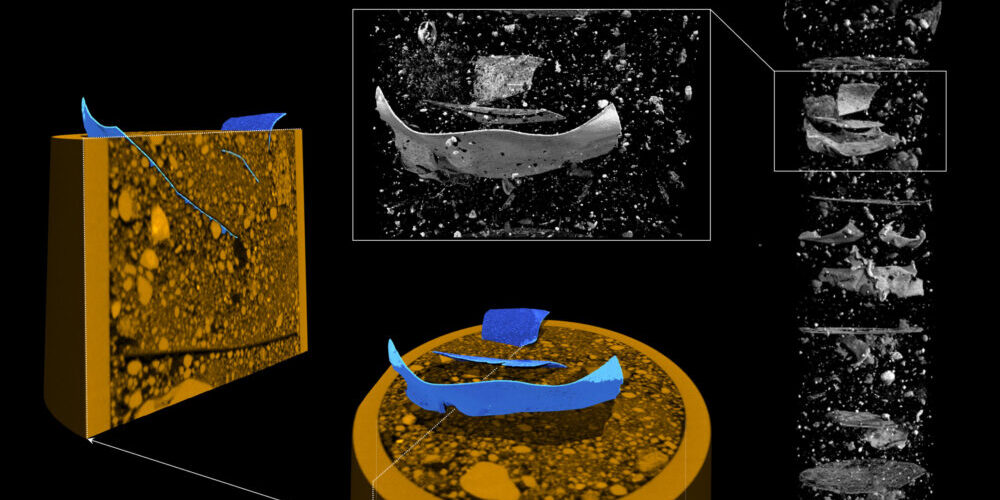

Auch Forscherinnen und Forscher aus Wien haben bestätigt, dass winzige Plastikpartikel aus Lebensmitteln tatsächlich bis ins Gehirn gelangen können. In einem Experiment wurden Mäuse von einem Team der MedUni Wien mit Mikro- und Nanopartikeln (MNP) aus Polystyrol gefüttert, dem Kunststoff, aus dem Styropor hergestellt wird.

Erstaunlicherweise konnten bereits zwei Stunden nach der Fütterung 0,293 Mikrometer große Nanopartikel aus Styropor im Gehirn der Mäuse nachgewiesen werden. Die Forschenden konnten jedoch keine größeren Partikel oder Mikroplastik nachweisen. Nanoplastik ist definiert als Plastikteilchen, die kleiner als ein Mikrometer oder 0,001 Millimeter sind.